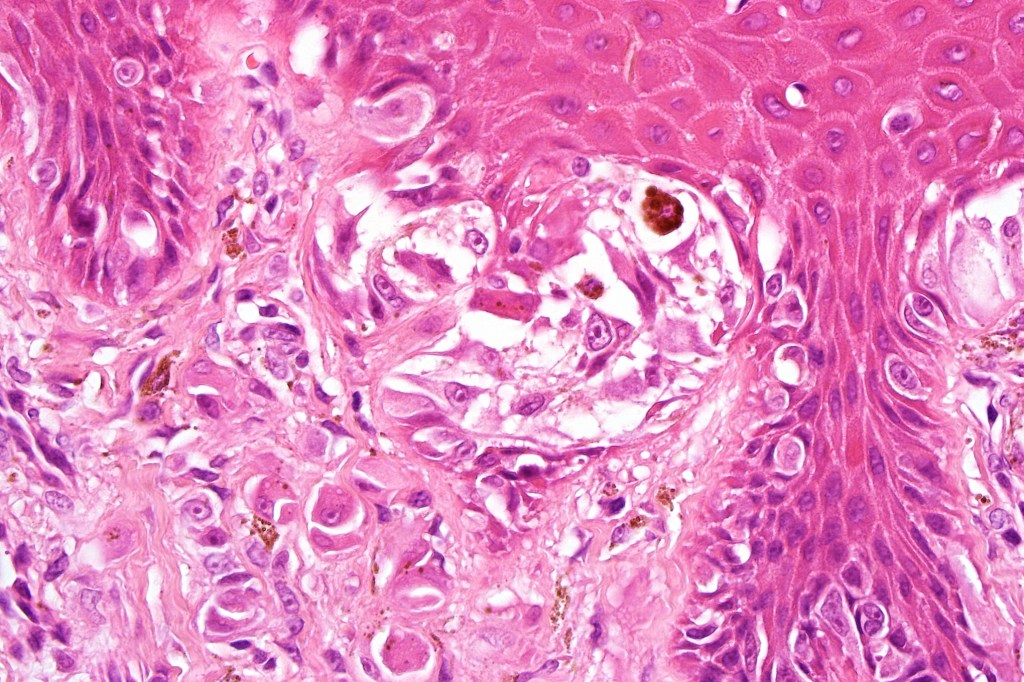

•Junctional nests often vertically orientated, dyscohesive with a surrounding retraction artifact

•Pleomorphism is almost invariable but affects all of the population to the same extent i.e., the cells & nuclei all look very much the same

•Epithelioid cell variants often show greater pleomorphism and cells can frequently appear bizarre with abundant, sometimes ground glass cytoplasm and large vesicular nuclei with prominent eosinophilic nucleoli, multinucleate cells are often seen

•Intracytoplasmic pseudoinclusions commonly present in epithelioid cells

•Kamino bodies (often multiple) are a characteristic feature